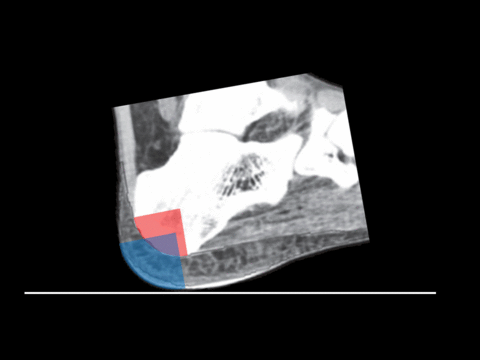

After quite a lot of head scratching we found out that the artefact (in how markers on the medial, posterior, and lateral calcaneus move) can be explained quite easily if the calcaneus rolls forward in the first 50ms or so of stance (and takes the rest of the foot with it). This makes quite a lot of sense as the foot is rotating quite fast (approx. 200°/s) immediately before foot contact and we know that the foot is lowered to the floor over approximately this period. When I went and looked at a few x-rays this seems to relate very well to the functional anatomy of the calcaneus which has an almost circular posterior-distal aspect in the sagittal plane (red quarter circle in animation below). A recent paper on the anatomy of the heel pad confirms that it too wraps around onto the posterior aspect of the calcaneus which would allow cushioning of the calcaneus throughout any such rolling motion (blue quarter circle in animation below). I’ve not seen this mechanism described in exactly this way before but it is, of course, very similar to the Perry’s first rocker of stance.